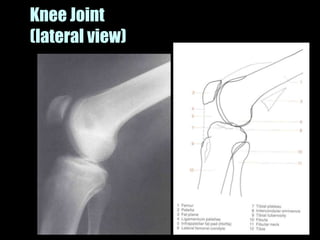

This document provides an overview of normal musculoskeletal imaging. It discusses basic x-ray concepts and densities. It then reviews normal anatomy as seen on x-rays of the skull, spine, pelvis, chest, and extremities. Key anatomical structures are labeled on example x-rays for the shoulder, hip, knee, and foot. Quizzes are included to test recognition of anatomical structures and patient age based on x-rays.